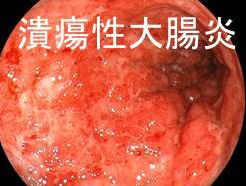

以前、日本人には少なく、欧米人に多いと言われていた炎症性腸疾患[クローン病(Crohn 病)と潰瘍性大腸炎(Ulcerative colitiss:UC)]。実は日本人にも多く、潰瘍性大腸炎(UC)22万人以上(厚生労働省指定の難病で最多)、クローン病(Crohn 病) 7万人以上と推定されます。日本の潰瘍性大腸炎(UC)患者数はアメリカに次いで世界第2位です。

潰瘍性大腸炎(UC)・クローン病(Crohn 病)ともに10-30歳代の若年者に多く、甲状腺の病気に合併すると、症状が増悪したりマスクされたりします。

潰瘍性大腸炎(UC)は大腸の炎症で、直腸から連続して口側に向かい病変が広がります(一方、クローン病(Crohn 病)は小腸と大腸の炎症です)。病変の範囲により、①全大腸炎(最多)、②左側大腸炎、③直腸炎に分けられます。

クローン病(Crohn 病)は腸管全層の炎症ですが、潰瘍性大腸炎(UC)は大腸粘膜上皮に限局した炎症。

潰瘍性大腸炎(UC)と甲状腺

潰瘍性大腸炎(UC)は抗大腸抗体・抗ムチン抗体・抗好中球細胞質抗体(ANCA)などの自己免疫抗体による大腸粘膜障害とされ(外科 66;754―758:2004)、バセドウ病と同じく抗体産生中心のTh2優位免疫です (Curr Opin Gastroenterol. 1999 Jul;15(4):291-7.)。

潰瘍性大腸炎(UC)における甲状腺疾患の合併率は、健常人の2-4倍とされます(Q J Med. 1989 Sep;72(269):835-40.)。しかしながら、甲状腺機能亢進症/バセドウ病の合併率は、高いとする報告と否定的な報告の両方があります(Eur Rev Med Pharmacol Sci. 2016;20(4):685-8.)。

甲状腺機能亢進症/バセドウ病患者で、甲状腺ホルモンが安定しても軟便・下痢が続く場合は潰瘍性大腸炎(UC)の合併を、潰瘍性大腸炎(UC)患者で下痢・頻脈・体重減少が強い場合には甲状腺機能亢進症/バセドウ病の合併を疑うべきです。